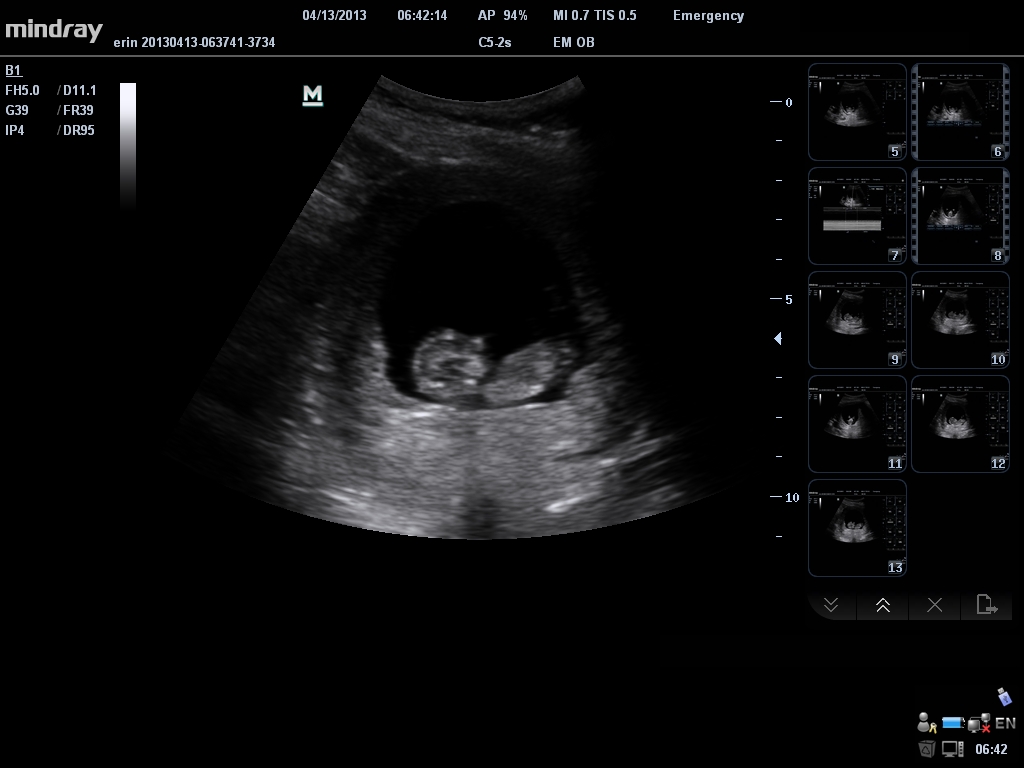

The US tech did not give me great photos...but thought I would try anyways to see if anyone has a guess. Thanks in advance!